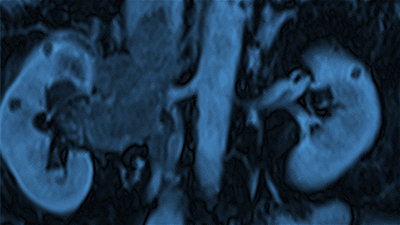

麻省总医院的泌尿科致力于在泌尿科护理方面实现临床卓越。我们为男性泌尿生殖道和女性泌尿道疾病提供以患者为中心的尖端治疗。

我们为患有任何类型泌尿系统疾病的患者提供成熟、人性化的护理和前沿的治疗。

麻省总医院泌尿科致力于以富有同情心,安全和以患者为中心的方式提供高质量的患者护理。

每年,我们的医生都会进行 5,000 多个泌尿外科手术。

泌尿外科致力于通过创新和突破性的研究来推进泌尿外科领域,以改善泌尿系统疾病的诊断和治疗。